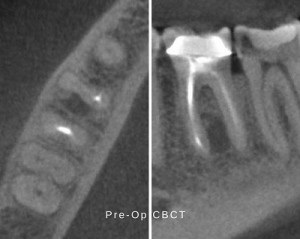

In mid-January 2016, a patient presented to our office, following referral from their general dentist, in pain from a lower right first molar. The tooth had been previously treated and had recently become exquisitely painful to percussion and palpation. It had a full coverage restoration with normal mobility and probing depths. Radiographs of the tooth showed a radiolucent lesion (lesion of endodontic origin) contiguous with the mesial roots. Interestingly, the lesion was located in the apical half and furcal side of the mesial root.

Our understanding of the pathogenesis of lesions of endodontic origin (LEO) would suggest that there was a portal of exit that was near the center of the lesion, allowing bacterial toxins to diffuse into the attachment apparatus (PDL).

Given my expectation of an ancillary exit point of the root canal system, it became apparent that surgical apicoectomy would entail removal of a significant portion of the mesial root to incorporate this portal of exit. With this in mind the decision was made, with the patient’s approval, was for conventional endodontic retreatment.